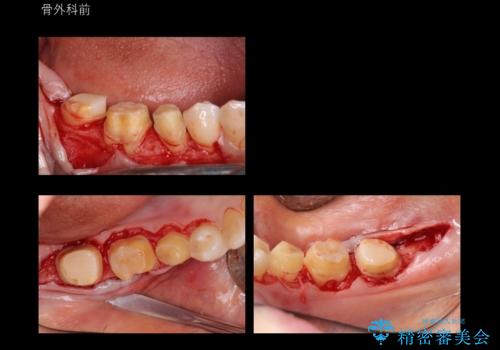

奥歯の高さがない 歯周外科で解決

- 右下奥歯(7番)の高さがなく、かぶせ物(クラウン)にするためにあらかじめ歯周外科手術を行いました。(クラウンレングスニング)

右下5番は歯ぐき付近までWSD(くさび状欠損)で削れていたため、患者様と相談してクラウンにしました。その際、削れていたのが歯肉縁下に及んでいたため、一緒に手術範囲に含めました。